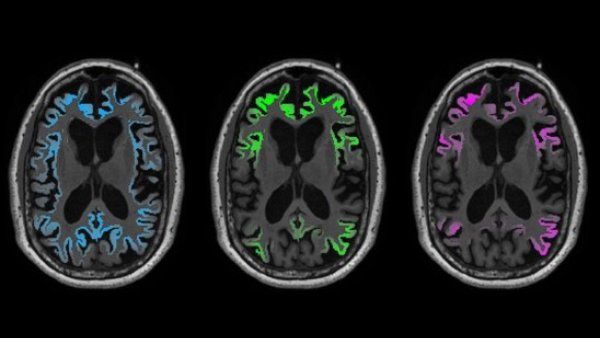

Alzheimer ‘Tau’ Protein Far Surpasses Amyloid in Predicting Toll on Brain Tissue